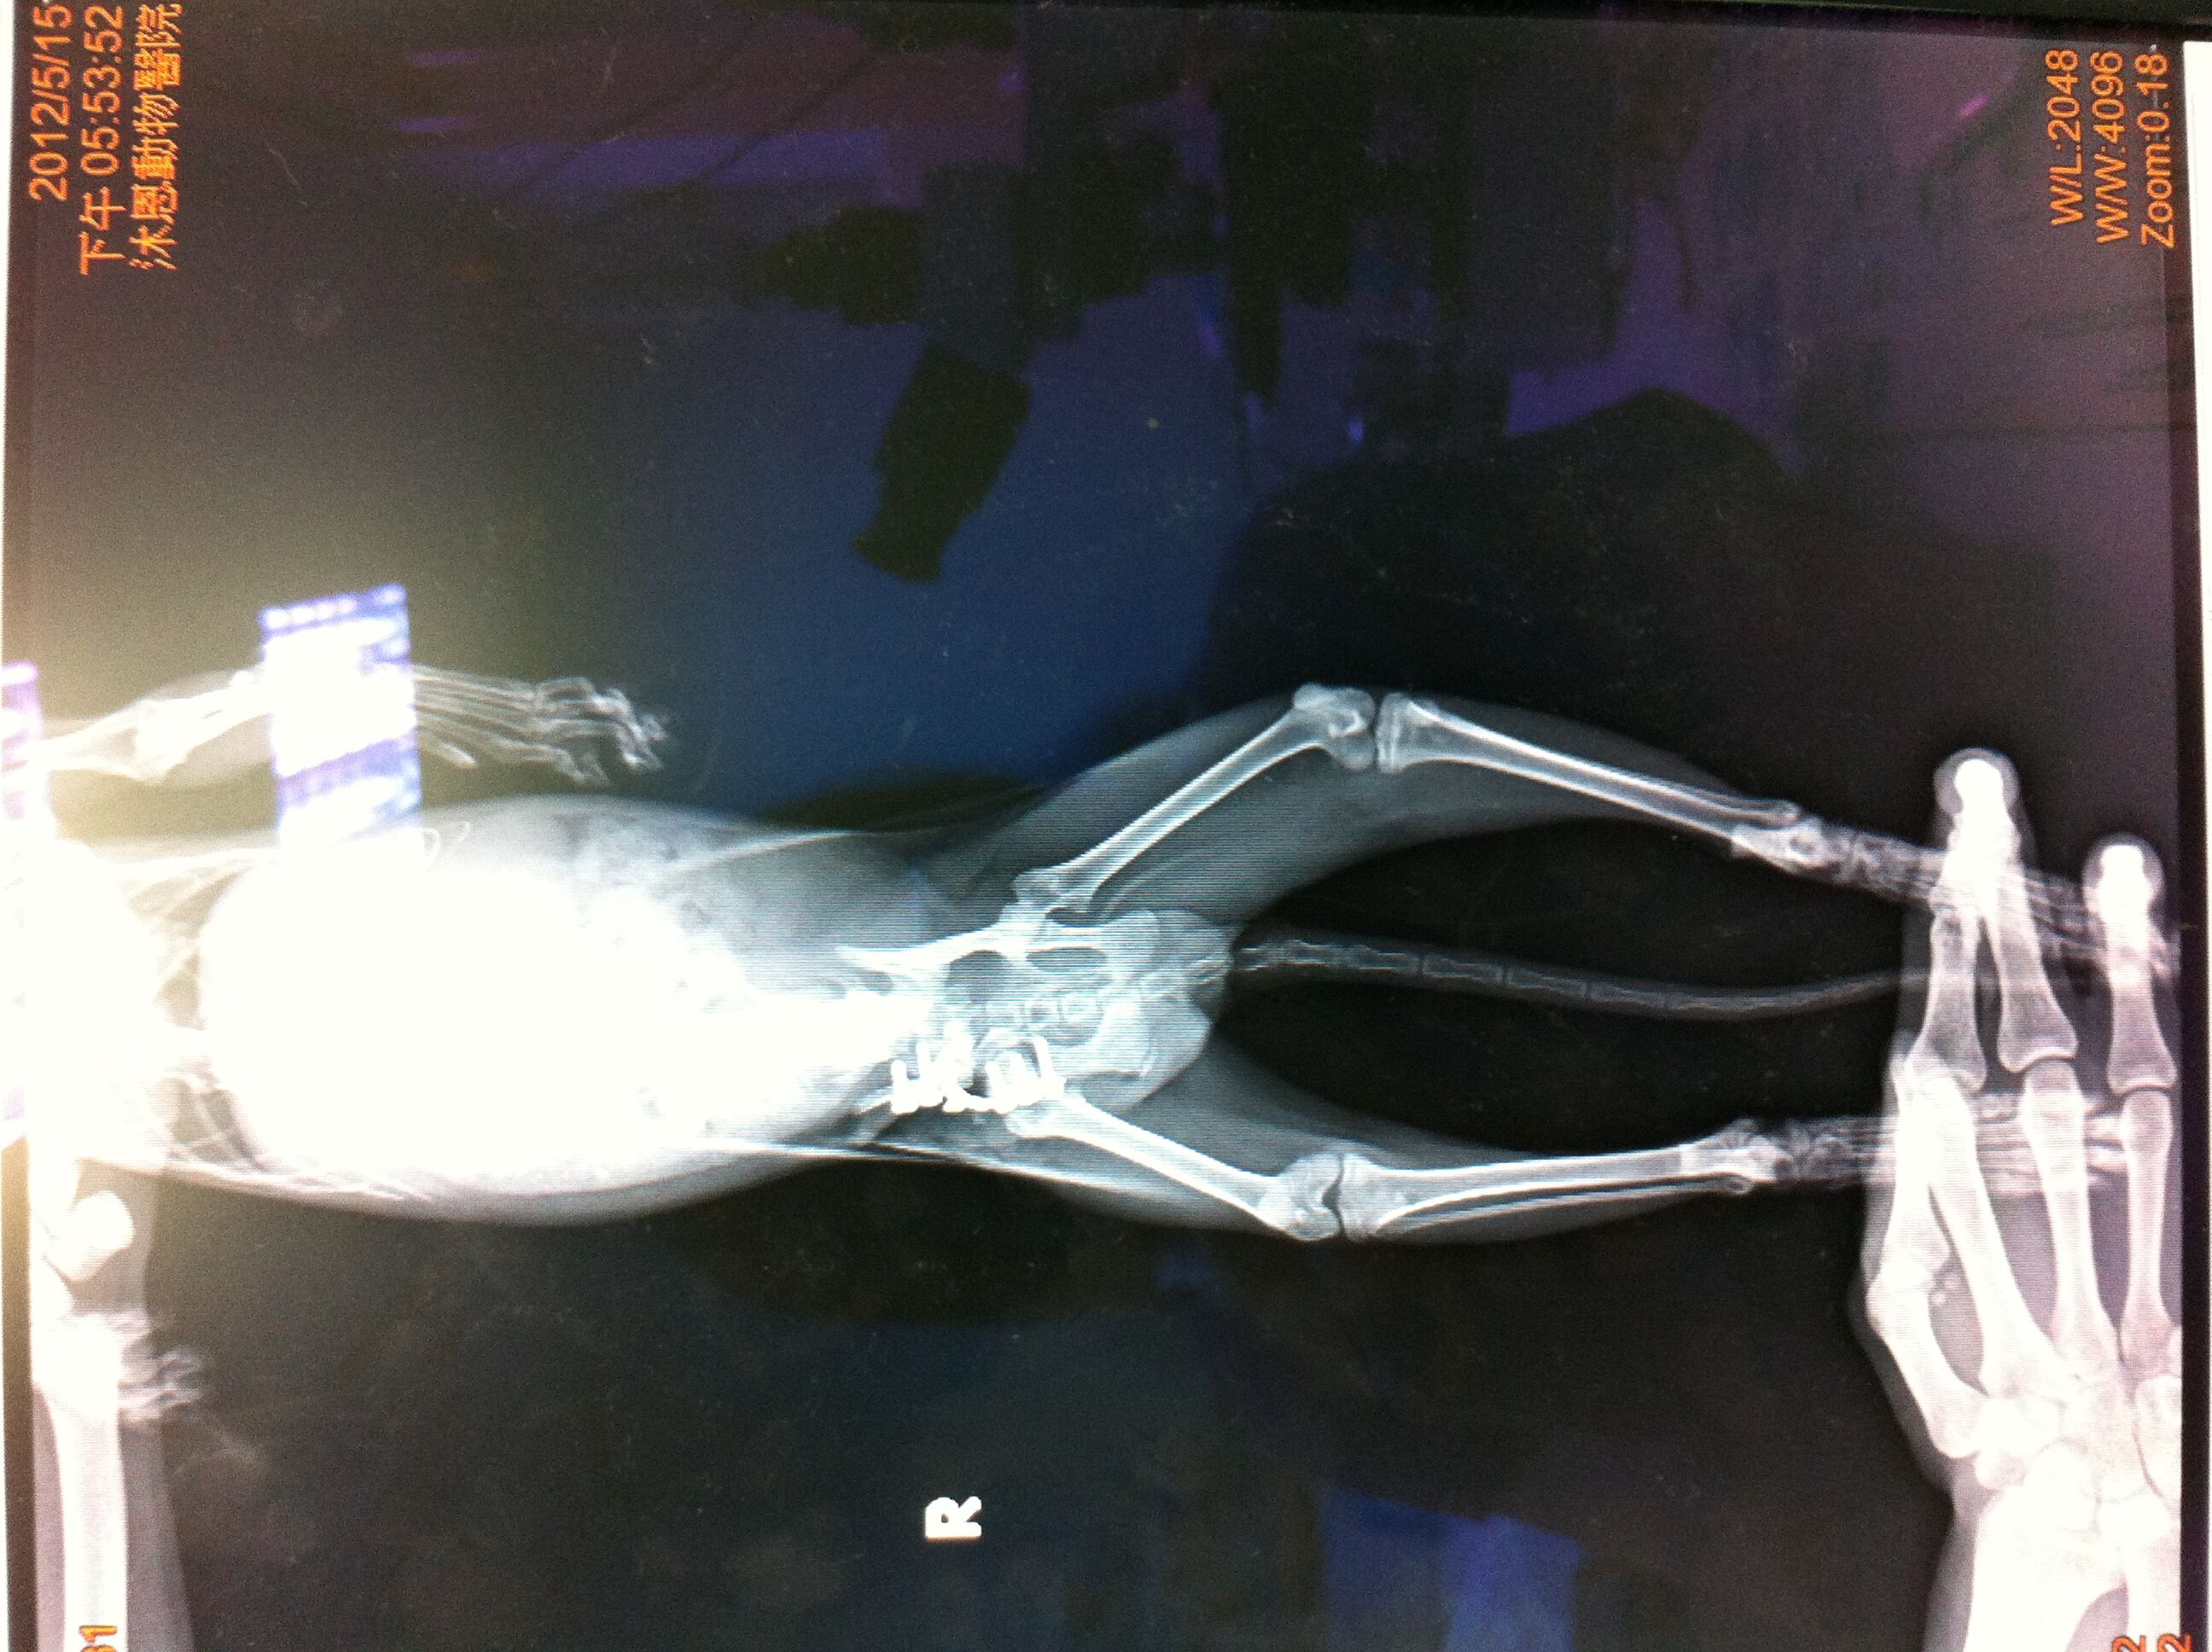

主題: 恥骨骨折骨盆狹窄併腸阻塞的車禍小貓(第2次招募,第1次編號326) 申請者姓名: 張嘉盈 花色: 申請日期: 2012-05-20 18:39:50 申請者部落格: 申請者臉書網址: http://facebook.com/chiayng 所在縣市/合作醫院: 台北市/其他院所醫助專案(醫院請先MAIL溝通) 治療費用: 6252元 需求人數: 16人 已結案 (2012-06-22 00:09:21) 報名人員: Cookie(已付款)、Cookie(已付款)、suxiwen(已付款)、suxiwen(已付款)、suxiwen(已付款)、suxiwen(已付款)、suxiwen(已付款)、yuchi(已付款)、yuchi(已付款)、yuchi(已付款)、yuchi(已付款)、yuchi(已付款)、Huang Mark(已付款)、Yi Chen Hsieh(已付款)、hunter0508s(已付款)、Justin Verlander(已付款)、 候補人員: Crystal Huang、小舟、小舟、 動物病情說明: (醫療款不足,此為第2次招募,第1次編號326)

中和區的黃愛媽發現餵養的4個月流浪小貓很虛弱癱軟,腹部異常脹大,礙於經濟因素也未帶小貓就醫,志工知道後先自費代小貓就醫,醫生表示觸摸有腸阻塞情形,很可能需要開刀治療,先開藥服用,但隔日小貓一直有用力如廁樣,非常痛苦仍解不出糞便,下面出不去上面也進不來,非常虛弱,5/9緊急通報協會送往沐恩動物醫院,骨盆狹窄無法指診,照x光確定骨盆骨折至少10天以上,醫生研判是車禍外力導致腸骨(iliac)骨折凹陷,骨盆口直徑只剩0.8公分,完全無法排便,已麻醉通腸挖糞,但一定要手術將骨盆口打開否則終生無法排便,5/1行骨盆矯正手術,植入鋼板,她雖然有點虛弱,且碰到屁屁會痛,但是看到人會拼命站起來撒嬌